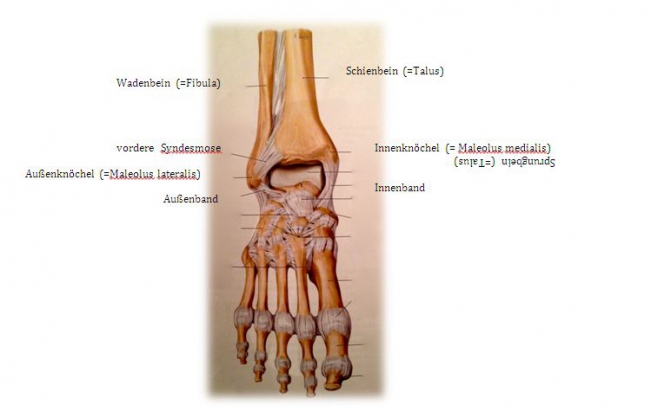

If one speaks of the ankle joint, one actually speaks of the "upper ankle joint". It is formed by three bones: Shin bone (= tibia), fibula and talus. Shinbone and fibula form a bony fork (= malleolus fork), which surrounds the anklebone in a U-shape. The upper ankle joint allows the foot to be raised and lowered.

The outer ankle is the joint process of the fibula, the inner ankle is the joint process of the tibia. A complex ligamentous apparatus ensures the stability of the ankle joint: outer ligaments, inner ligaments and anterior and posterior syndesmosis (= a very firm ligament connection between the tibia and fibula).

undefined

Fig.1) Anatomy of the upper ankle joint (from: Prometheus ®, MLP)